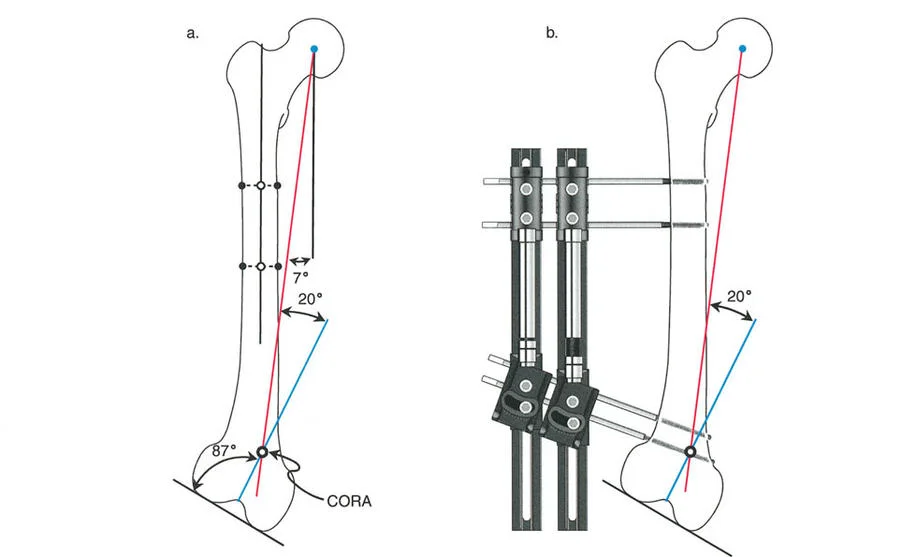

المفصلات القريبة من المفصل وقواعد قطع العظم (Osteotomy Rules)

عند التعامل مع التشوهات الواقعة بالقرب من خط المفصل - مثل التقوس الشديد في الجزء العلوي من الساق (مرض بلونت) أو التشوه الفحجي في الجزء السفلي من عظم الفخذ - يصبح وضع الجهاز مقيدًا هندسيًا. إن المتطلبات البيولوجية للحفاظ على كبسولة المفصل، وتجنب وضع الأسلاك داخل المفصل، ومنع التهاب المفاصل القيحي، غالبًا ما تجبر الجراح على وضع الحلقة المرجعية على مستوى مختلف تمامًا عن مركز دوران الانحراف (CORA) الفعلي.

تحدي مركز دوران الانحراف (CORA) القريب من المفصل

لمطابقة مفصلة المثبت الخارجي مع المستوى الدقيق لمركز دوران الانحراف (CORA)، يجب غالبًا بناء المفصلة فوق أو تحت مستوى الحلقة الفعلية. يُعرف هذا في مبادئ بالي باسم تجميع المفصلة القريبة من المفصل (juxta-articular hinge assembly).

إذا كان مركز دوران الانحراف (CORA) يقع بالقرب من خط المفصل، فإن وضع حلقة إليزاروف القياسية عند هذا المستوى بالضبط مستحيل دون انتهاك مساحة المفصل أو شد الهياكل الكبسولية الحيوية. لذلك، يتم تثبيت الحلقة المرجعية بالعظم الكثيف أو العظم الطويل المتاح، ويتم بناء آلية المفصلة باستخدام قضبان ملولبة، ولوحات توصيل، ودعامات. ثم يتم "إنزالها" (أو رفعها) لتتطابق تمامًا مع مركز دوران الانحراف (CORA) الهندسي الحقيقي.

قواعد بالي لقطع العظم (Osteotomy Rules) في وضع الأجهزة

فهم قواعد بالي لقطع العظم أمر لا غنى عنه لتخطيط الإطار:

- قاعدة قطع العظم 1: عندما يمر قطع العظم ومحور تصحيح الانحراف (ACA) كلاهما عبر مركز دوران الانحراف (CORA)، فإن نهايات العظم ستنحرف دون ترجمة (انزياح). يتم استعادة المحور الميكانيكي، وتظل نهايات العظم متقاربة تمامًا، مما يخلق تصحيحًا كلاسيكيًا "إسفينيًا مفتوحًا" أو "إسفينيًا مغلقًا".

- قاعدة قطع العظم 2: عندما يمر محور تصحيح الانحراف (ACA) عبر مركز دوران الانحراف (CORA)، ولكن يتم إجراء قطع العظم على مستوى مختلف (غالبًا بسبب ضعف جودة العظم عند CORA أو مشاكل في الجلد)، فإن نهايات العظم ستنحرف وتخضع لترجمة محسوبة ومقصودة لإعادة محاذاة المحور الميكانيكي.

- قاعدة قطع العظم 3: (للاكمال) عندما يمر قطع العظم عبر مركز دوران الانحراف (CORA)، ولكن يتم وضع محور تصحيح الانحراف (ACA) خارج CORA، سيتم إنشاء تشوه ترجمة جديد، وهو خطأ شائع في وضع المفصلات غير المخطط له جيدًا.

في المنشآت القريبة من المفصل، غالبًا ما نعتمد على قاعدة قطع العظم 2. نظرًا لأنه لا يمكننا قطع العظم بأمان عند خط المفصل تمامًا (مركز دوران الانحراف CORA)، فإننا نقطع العظم في مستوى أدنى في منطقة الميتافيسيس. بعد تحقيق التصحيح الزاوي عبر المفصلات (محور تصحيح الانحراف ACA)، يتم إعادة محاذاة خطوط المحور الميكانيكي بشكل مثالي، ولكن نهايات العظم في موقع قطع العظم تتحرك بالنسبة لبعضها البعض.

نصائح جراحية للمنشآت القريبة من المفصل

| المبدأ | التطبيق السريري | تحذير / خطأ محتمل |

|---|---|---|

| التحقق من CORA | دائمًا تحقق من CORA الحقيقي في الأشعة السينية الطويلة للطرفين قبل بناء المفصلة. | الاعتماد على الأشعة السينية القصيرة للركبة سيؤدي إلى CORA غير دقيق وبالتالي سوء محاذاة. |

| ACA العمودي | تأكد من أن محور المفصلة (ACA) عمودي تمامًا على مستوى التشوه. | محور ACA مائل سيحدث تشوهًا ثانويًا غير مرغوب فيه (مثل تصحيح التقوس ولكن إحداث الانحناء الأمامي). |

| تخليص الأنسجة الرخوة | عند استخدام قاعدة قطع العظم 2، احسب الترجمة المتوقعة وتأكد من أن الأنسجة الرخوة يمكن أن تستوعبها. | عدم مراعاة الترجمة يمكن أن يتسبب في اصطدام العظم بالجلد، مما يؤدي إلى النخر. |

| تقابل الأسلاك | استخدم ما لا يقل عن سلكين زيتون متقابلين لكل قطعة إذا كنت تتجنب الدبابيس النصفية. | الأسلاك الزيتون الفردية ستسبب قصًا ودورانًا غير مرغوب فيه حول محور السلك. |